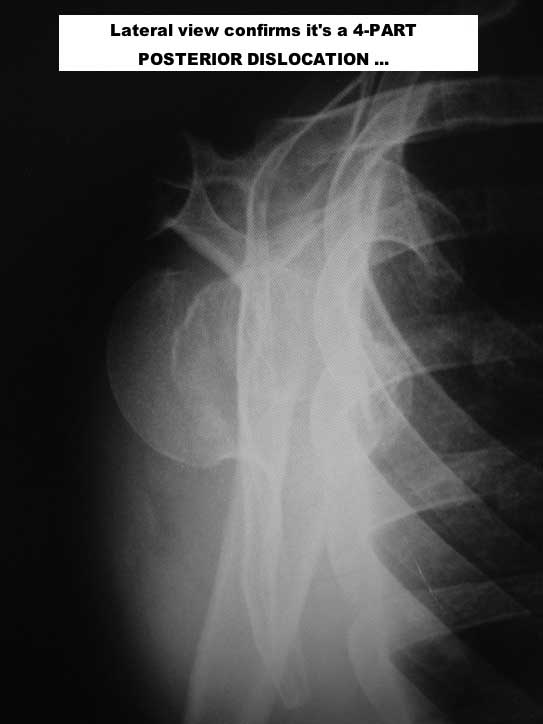

1) This a chronic, 4-part anterior fracture dislocation. How do I know it is anterior, and not posterior, only with a plain AP X-ray ??

Because posterior dislocations do not behave this way, radiographically, believe me. Also, there MAY be an A-C TYPE V dislocation in this shoulder ... But. let's forget that, now ...

Here are some photos, of chronic, locked, 4 part posterior dislocation, 2 months old, that I did September/2011. Patient is 67, very, very active - had a really reasonable, honest clinical result ...

Photos attached ...